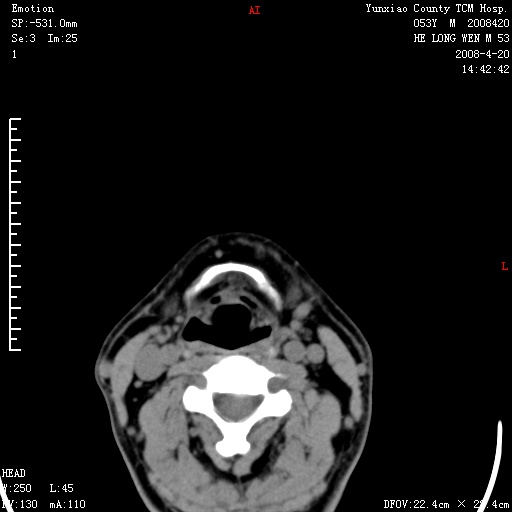

双侧扁桃体肿大:考虑化脓性扁桃体炎。

双侧扁桃体肿大 ,考虑扁桃体炎。

双侧扁桃体肿大,建议结合临床!

双侧扁桃体肿大 ,考虑扁桃体炎

应该有症状,体检此部位不是常规体检项目,支持双侧扁桃体肿大 ,考虑扁桃体炎,但还是强化一下吧。

双侧扁桃体肿大,考虑扁桃体炎,应做一下增强

显示部分为舌扁桃体,腭扁桃体未见显示。会厌显示欠规则,建议喉镜。